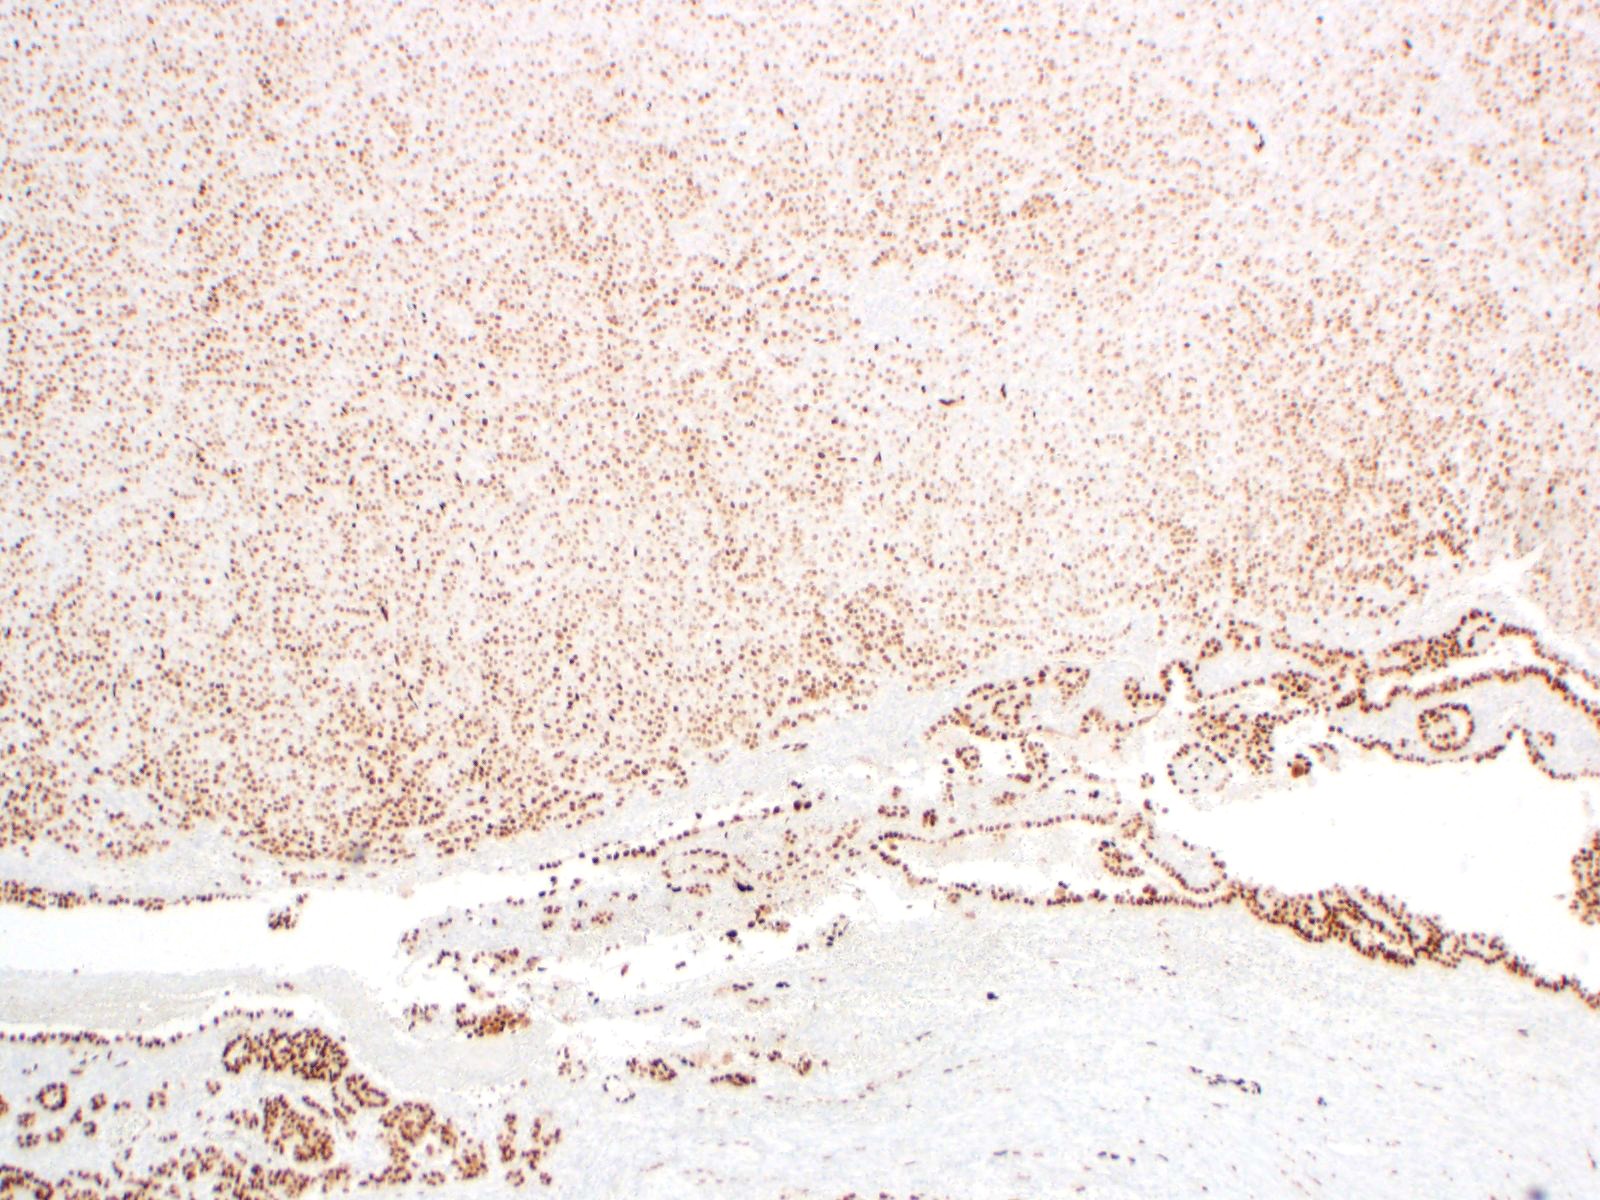

| 2SC |

S-(2-succino)-cysteine |

Rabbit polyclonal (Cambridge Research Biochemicals)

Hereditary leiomyomatosis and renal cell carcinoma (HLRCC) syndrome-associated RCC and leiomyoma

Most renal tumors and leiomyomas not associated with HLRCC

Staining Pattern

Cytoplasmic and nuclear

| HLRCC-associated RCC |

| Non-HLRCC-associated RCC |

| HLRCC-associated leiomyoma |